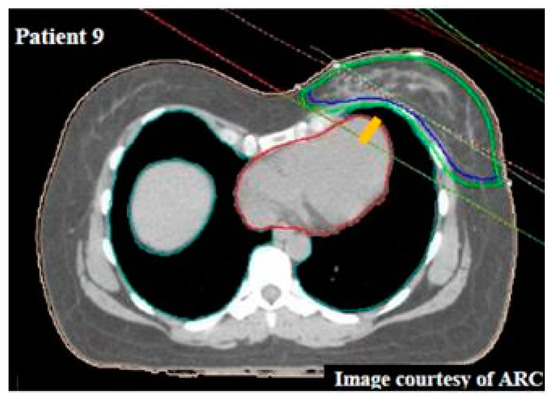

| 9 | Voluntary BH § | 2.8 | 7.8 | 5.3 | 3.0 | 9.6 | 34.6 | 25.0 | 37.9 | −1.1 | −0.9 |

| 9 | 2.1 | 3.1 | 1 | 2336 | 4277 | 1941 | 1.9 | 1.2 | 0.7 | 21.7 | 21.8 | −0.1 |

| 9 | 1941 | 1.2 | 5.3 | 4 | 3.8 | 3 | 9.6 | 37.9 | 25 | |